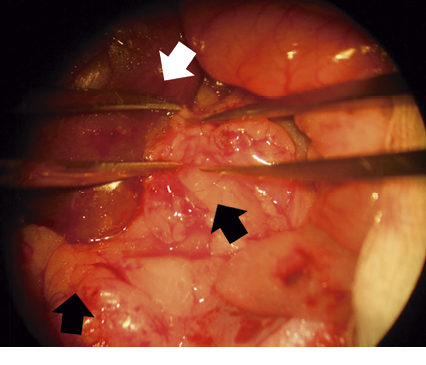

Surgery was carried out in two phases in the Ob/KF group. Firstly, ischemia was induced in the left kidney. Each rat was laid on its side and the abdominal cavity was dissected. Parts of the intestine were eviscerated to facilitate the exposure of the kidney at the hilum. The anterior and media branches of the kidney artery were tied together, leaving the posterior branch viable to enable the kidney to function. The second part of surgery was the removal of the right kidney after a paramedian laparotomy (at 2 cm from the median line). This incision was made because it heals quickly. A part of the intestine was eviscerated to locate the hilum of the kidney, and then the kidney artery and vein were individually tied, as was the ureter. Then the nephrectomy was carried out, and animals recovered for 8 weeks before sacrifice.

Due to the large quantity of fat in obese rats, adipose tissue represented a difficult problem in surgery. Therefore, 30% more anesthesia was employed with these animals (figure 1). At approximately 10 days after the second surgery, coarse and wiry hair of a yellowish color was noted on rats, as well as slight inflammation at the metatarsus (without difficulty in hind leg function). Kidney damage was confirmed by an increase in creatinine levels and blood pressure (table 1).

With the care taken in the surgery of the present study, there was a 90% survival rate of animals, despite hypertension and metabolic changes (in cholesterol, triglycerides, insulin and creatinine). Great care was taken to deal with the increase in adipose tissue in the abdominal cavity and at the periphery of the kidney, as well as the abundance of connective tissue between the kidney artery and vein (complicating the separation of both vessels) that is typical of rats at 6 months of age (figure 1). In some studies, involving 5/6 kidney surgery, anti-hypertensive drugs are administered or the diet used is low in sodium,18,19 which was not the case in the present study.